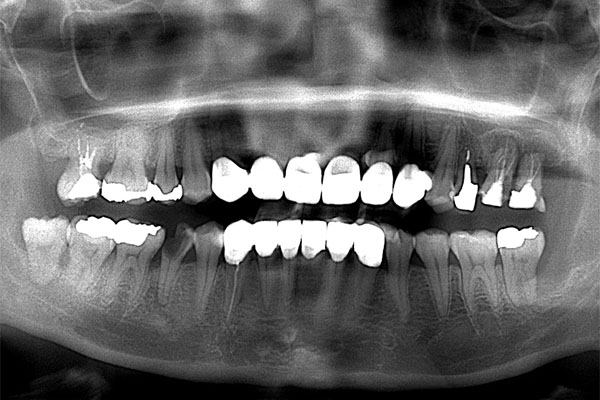

上顎左側第一・第二大臼歯は歯周病と根尖性歯周炎により保存不可能。また上顎左側第二小臼歯は縁下カリエス(根の虫歯)と短根のため部分矯正もできず予後不良と診断、抜歯をする経緯となりました。前歯部にはクラウンでの補綴修復が見られ下顎右側臼歯部には大きなカリエス様透過像が見られました。

【担当医師所見】

コーンビームCT像を確認すると左側上顎の骨は無くインプラント埋入の際は上顎骨に骨造成が必要と思われたため上顎洞挙上術(サイナスリフト)を併用、インプラント埋入を行うプランとしました。

また欠損部位の大きさを考えるとサージカルガイドの使用が必要と思われたため今回使用した。さらにオペの強度を考え静脈内鎮静法下にてオペを行った。

処置前では黒い透過像(骨が無い)があるが骨造成後1年経過、インプラントテック(仮歯)を入れた際では上顎洞内及びインプラント周囲に白い不透過像(骨がある)が確認できます。